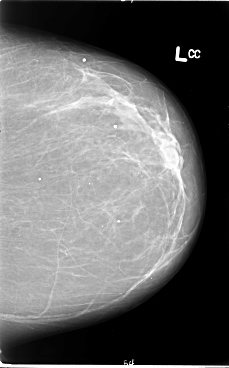

ics_version 1.0 filename B-3065-1 DATE_OF_STUDY 14 3 1994 PATIENT_AGE 69 FILM FILM_TYPE REGULAR DENSITY 2 DATE_DIGITIZED 15 9 1997 DIGITIZER LUMISYS LASER SEQUENCE LEFT_CC LINES 5880 PIXELS_PER_LINE 3664 BITS_PER_PIXEL 12 RESOLUTION 50 NON_OVERLAY LEFT_MLO LINES 5856 PIXELS_PER_LINE 3864 BITS_PER_PIXEL 12 RESOLUTION 50 NON_OVERLAY RIGHT_CC LINES 5704 PIXELS_PER_LINE 3504 BITS_PER_PIXEL 12 RESOLUTION 50 OVERLAY RIGHT_MLO LINES 5736 PIXELS_PER_LINE 3576 BITS_PER_PIXEL 12 RESOLUTION 50 OVERLAY |